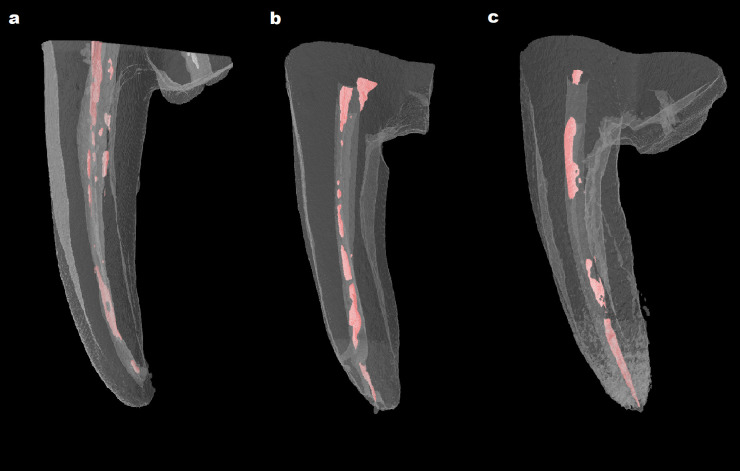

Methods: The curved mesio-buccal canals of extracted mandibular molars were prepared with the Protaper Gold file system (up to F2). Specimens were randomly divided into 3 groups and filled with the single cone technique using AH Plus, Well-Root ST, and AH Plus Bioceramic Sealer, respectively. After two weeks, the root canal filling of all specimens was removed using Protaper Universal retreatment files. All specimens were scanned using micro-CT. The remaining volume of the root canal filling was recorded in total and the coronal, middle, and apical third of each specimen.

Results: Well-Root ST and AH Plus Bioceramic Sealer groups had a higher percentage of total remaining filling material than the AH Plus group (P<0.05).

Conclusion: This study has shown that the volume of remaining root canal filling was significantly higher in the samples filled with calcium silicate-based sealers.